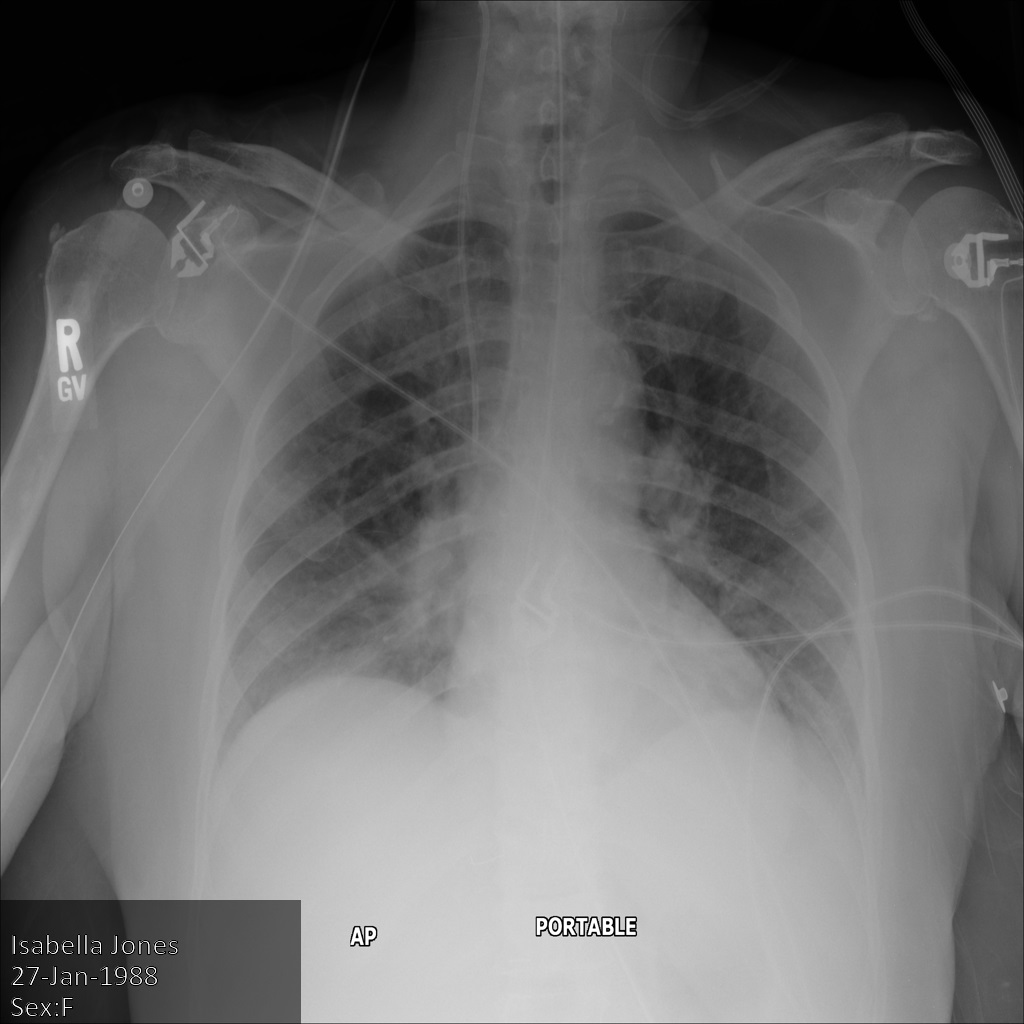

以下各節提供範例,說明如何使用各種方法去識別 DICOM 資料。每個樣本都會提供去識別化圖片的輸出內容。每個範例都會使用下列原始圖片做為輸入內容:

您可以比較各項去識別化作業的輸出圖片與原始圖片,瞭解作業效果。

將圖片提交給 Cloud Healthcare API 後,圖片會如下所示。雖然圖片頂端角落顯示的中繼資料已遭塗銷,但圖片底部的內建受保護健康資訊 (PHI) 仍存在。如要一併移除內建文字,請參閱「從圖片中遮蓋內建文字」。